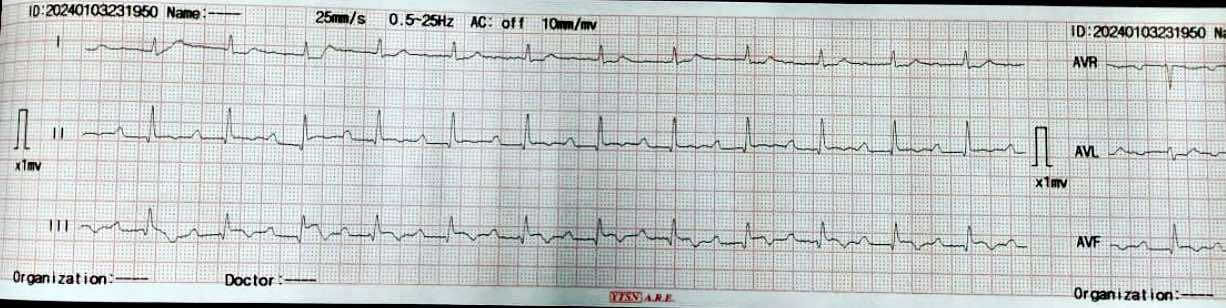

Male patient, 68 years old , Diabetic , Hypertensive .Ischemic heart disease with PCI to LAD 2 years ago .Recurrent chest pain with multiple admissions with ACS during the last 3 months for which coronary angiography was recommended ECG: SR with ST , T changes in inferior leads .ECHO: IHD with EF 52%, RSWMAs in the form of ( apical and Mid inferior and infero-septal wall hypokinesia ) with Moderate mitral valve incompetence BLPR: 140/90 mmHg , HR : 75 B/M , TEMP: 36.2 c , RBS : 258

Coronary angiography was done showing patent previous LAD stent and CTO RCA ** Symptomatic patient ** Good EF with SWMA at RCA territory ** Recurrent admissions with ACS And also Thallium study was done to document Ischemic burden of RCA territory and was positive